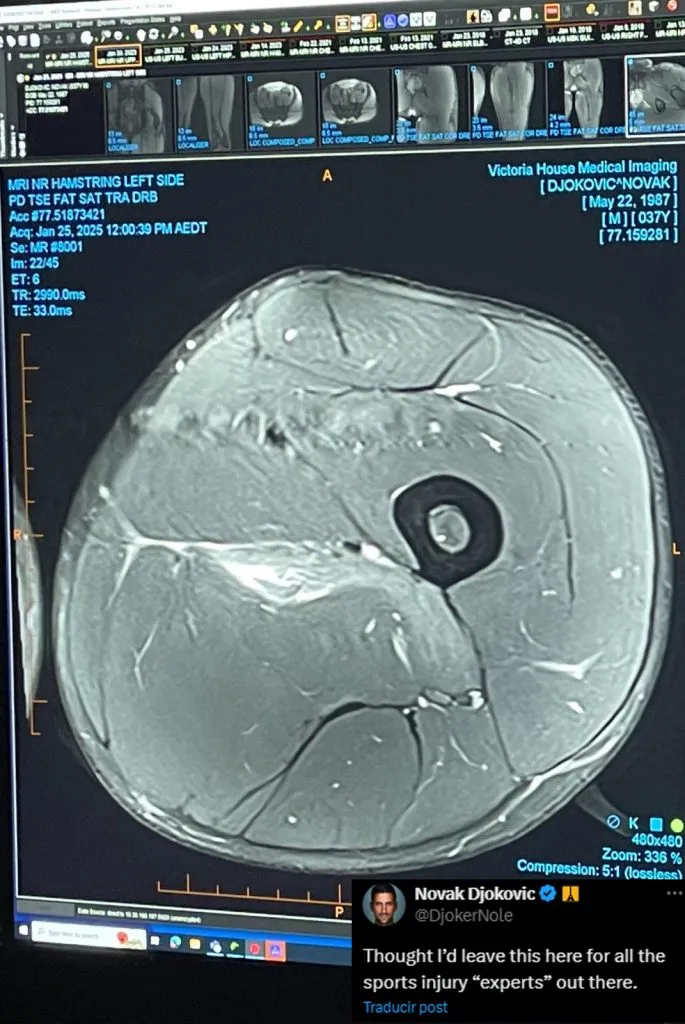

En su cuenta de X, Nole publicó una imagen de la resonancia magnética que muestra el desgarro que sufrió en el muslo de su pierna izquierda, y la acompañó de una particular dedicatoria. “Pensé en dejar esto aquí para todos los ‘expertos’ en lesiones deportivas que hay allí fuera”, apuntó.